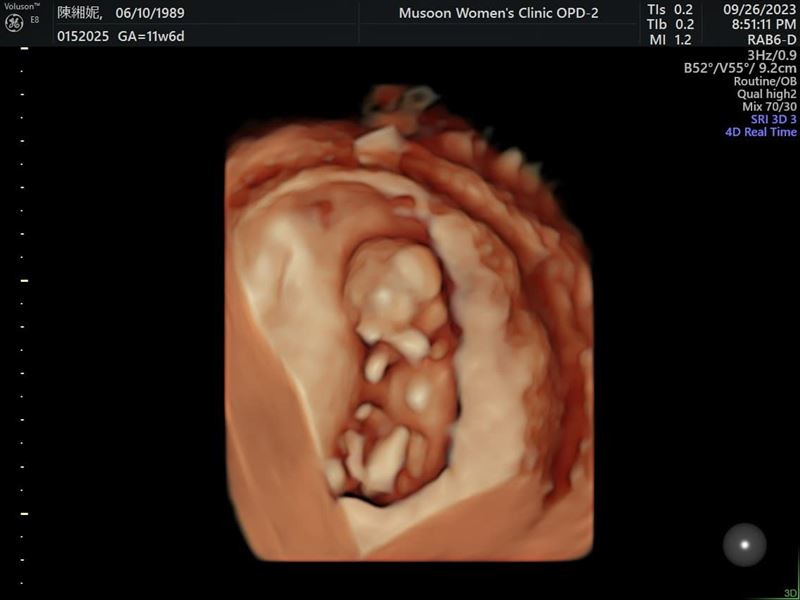

男星謝和弦去年與妻子莉婭(陳緗妮)生下愛女「謝音悅」後,上月底再宣布「又要當爸爸了」,還直呼自己是最幸運、最幸福的人。而他今(28)日貼出二寶的超音波照,透露依照預產期推估,孩子的星座將和他一樣是牡羊座。

▲謝和弦曬出二寶的超音波照片。(圖/翻攝自謝和弦臉書)

謝和弦表示,莉婭生育後身材不但恢復良好,而且變得更加漂亮,讓醫師直誇「這麼會生可以多生幾個」。於是兩人在生下女兒後,馬上又迎來第二個寶寶,預產期大約落在明年3至4月,和他一樣是牡羊座。對於孩子他則沒有特別的奢求,認為健康、善良就足夠了。